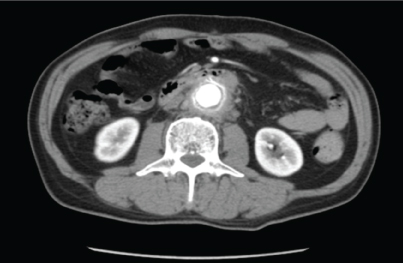

Abdominal computed tomography (CT) findings (Figure 2)

Increased adipose concentration was found around the abdominal aorta without clear boundaries. An inflammatory response or onset of retroperitoneal fibrosis was suspected.

Figure 2: Increased adipose concentration was found around the abdominal aorta without clear boundaries. Some inflammatory response or the onset of retroperitoneal fibrosis was suspected. View Figure 2